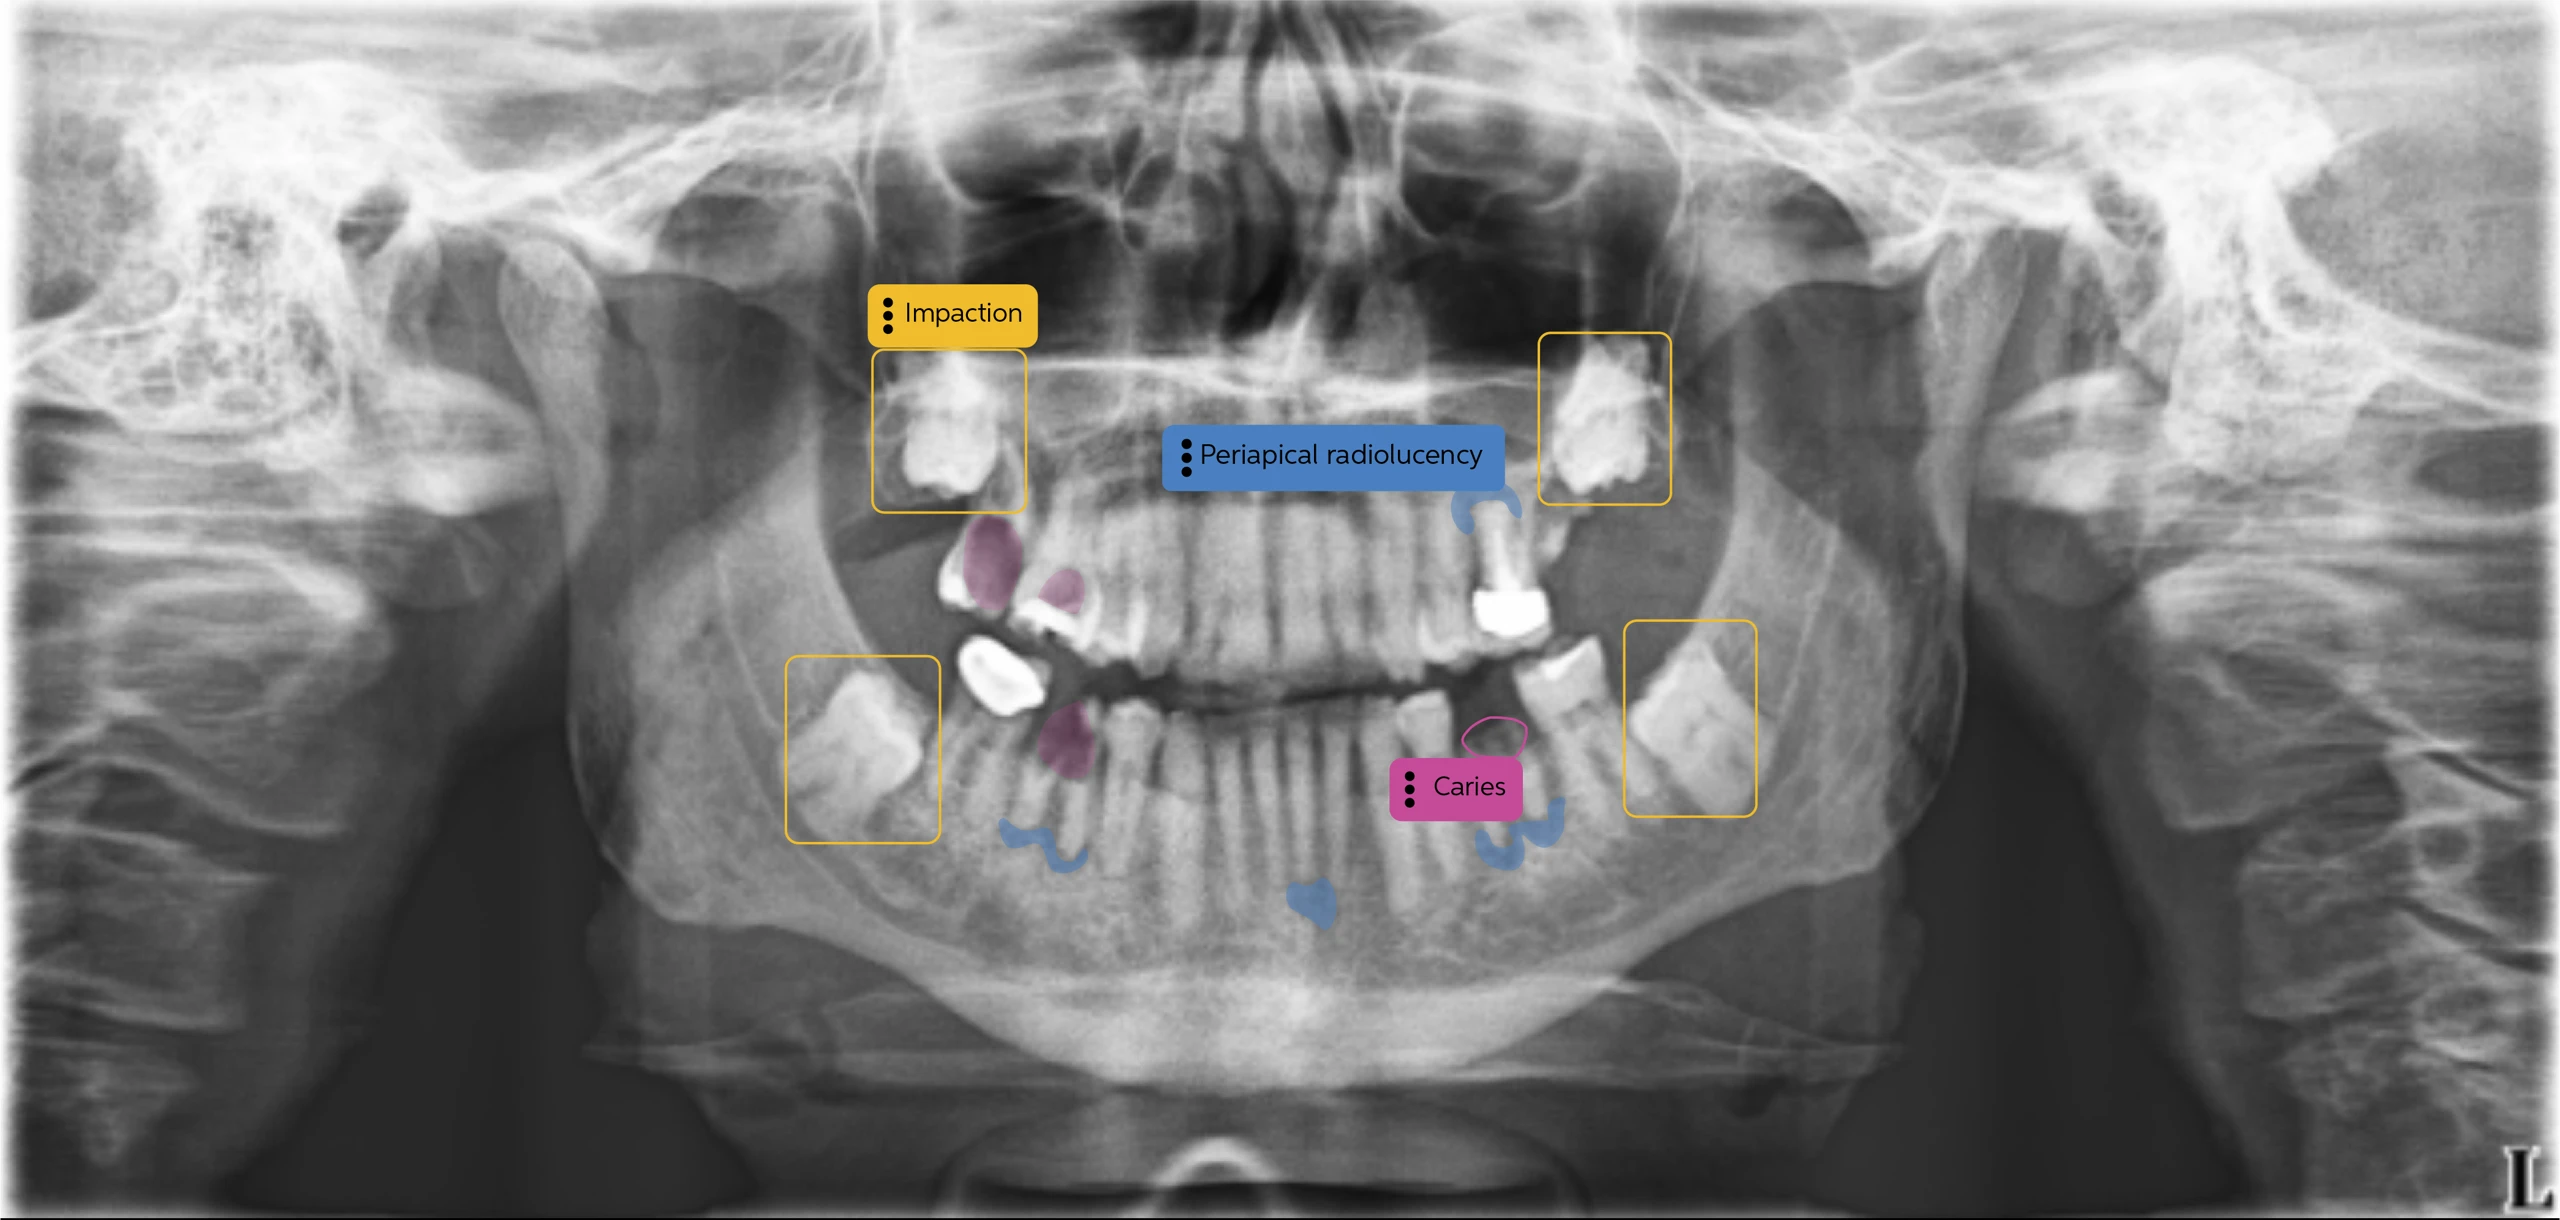

Pearl Dental AI is a cutting-edge artificial intelligence platform that acts as a second set of eyes, analyzing your X-rays with remarkable precision. This advanced technology helps us identify potential concerns earlier, ensure more consistent diagnoses, and ultimately, provide you with even more accurate and effective treatment plans.